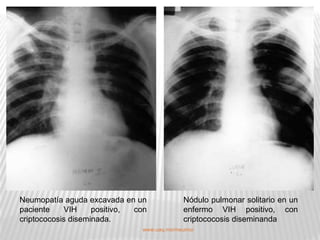

Neumopatía aguda excavada en un              Nódulo pulmonar solitario en un

paciente    VIH     positivo, con            enfermo VIH positivo, con

criptococosis diseminada.                    criptococosis diseminanda

www.uaq.mx/rneumo/